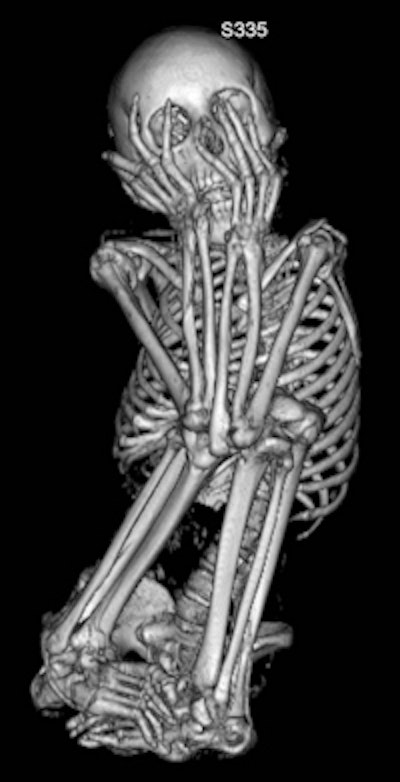

| This image, also of the 13-year-old female mummy, shows another view of the typical fetal position body placement. |

Sex and age of the mummies were determined by analyzing body structures such as the pelvis and skull, the authors wrote. Eight mummies were identified as female, three as male, and sex could not be determined for one. The ages of the mummies were newborn, 0.7 years, 2.5 years, 13 years, 13 years, and 16 years, with six mummies identified as being between 20 and 40 years old.

The height of the mummies, estimated by measuring femur and tibia length, ranged from 41 ± 3 cm (newborn) to 145 ± 14 cm (adult).